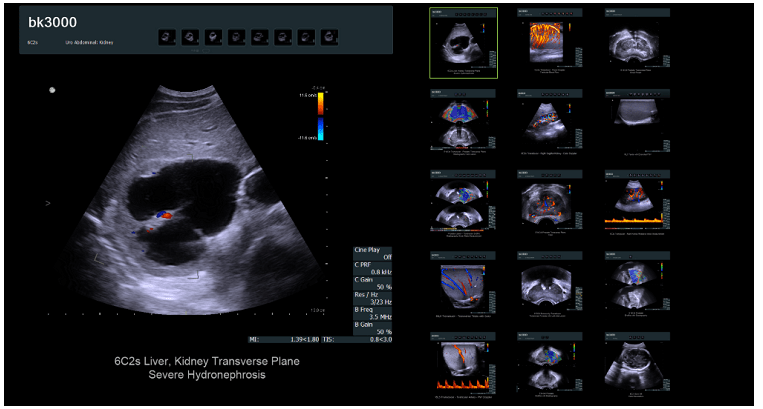

該在線商店出售現代且昂貴的設備(超聲波機器)。目標受眾不需要號召性用語,不需要標準的潛在客戶生成按鈕或評論形式的信任塊。產品的詳細和專業描述在這里起著關鍵作用,它將表明其功能,功能和優勢。

同意,此產品卡與我們以前所見的產品根本不同。但同時,它完全可以滿足目標受眾的需求。用于聯系賣家的潛在客戶生成按鈕促成銷售,并允許您增加網站的轉化率。